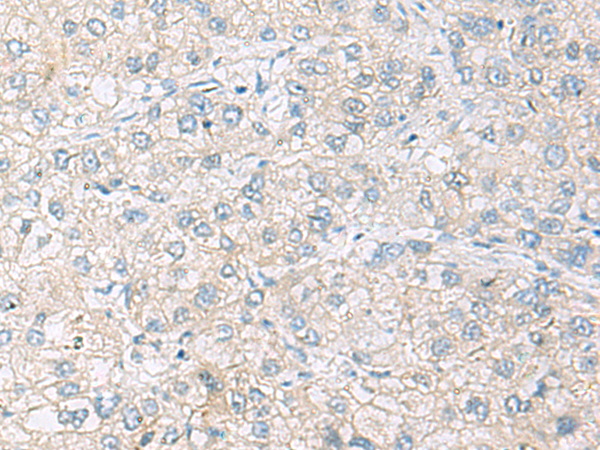

分类: 科研抗体货号: P10226别名:应用: WB,IHC反应种属: Human